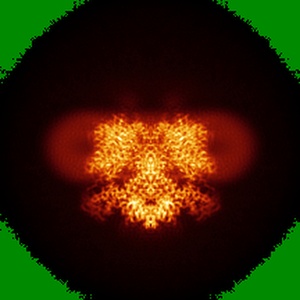

Down-regulated in adenoma in complex with TQR1122

structure of human SLC26A3 in complex with TQR1122